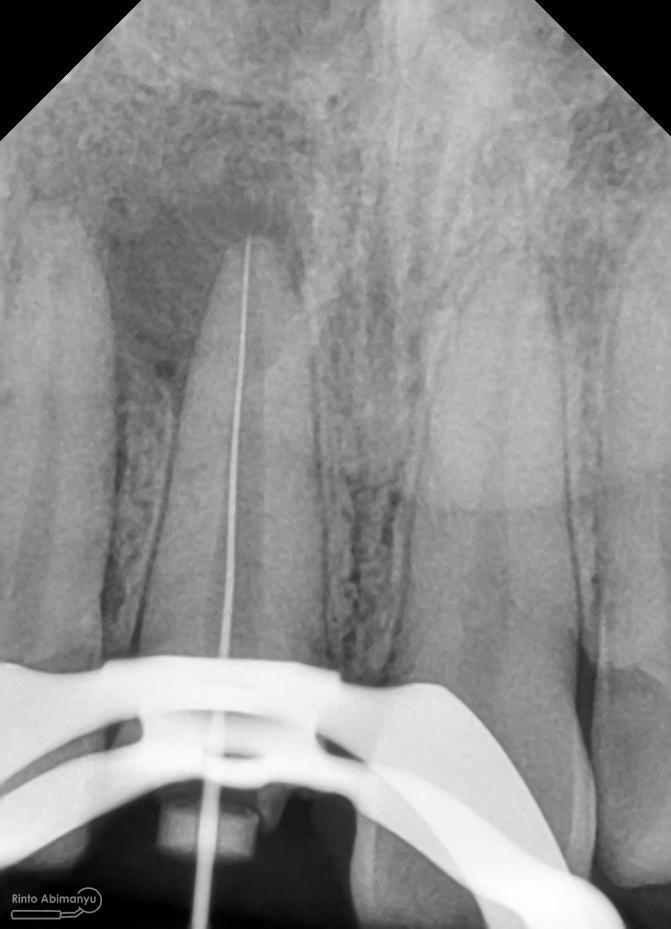

Kemudian dilakukan pengepasan guttap dan difoto ronsen….

Foto radiografis trial guttap